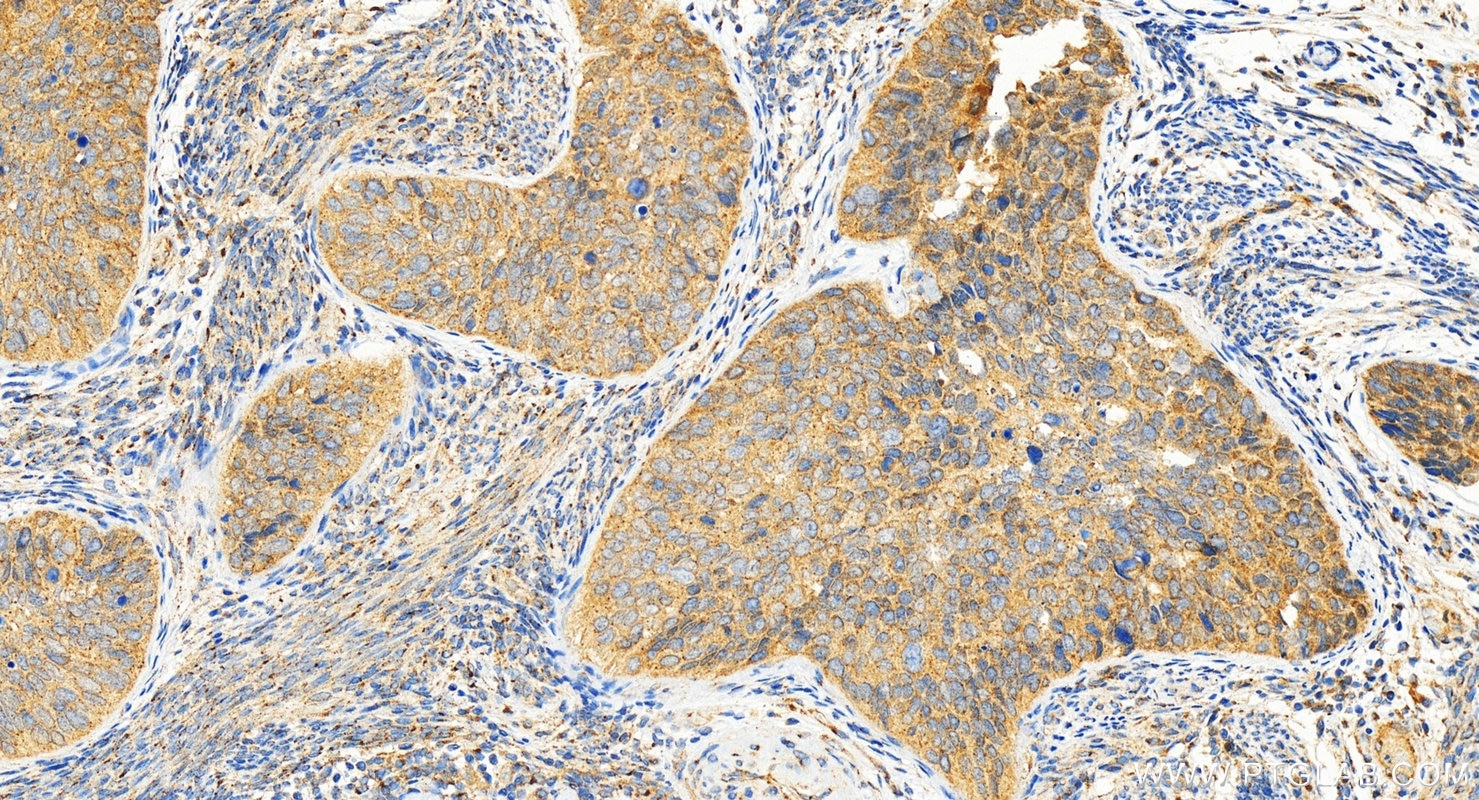

| Positive IHC detected in | human colon cancer tissue, human cervical cancer tissue Note: suggested antigen retrieval with TE buffer pH 9.0; (*) Alternatively, antigen retrieval may be performed with citrate buffer pH 6.0 |

| Immunohistochemistry (IHC) | IHC : 1:1000-1:4000 |